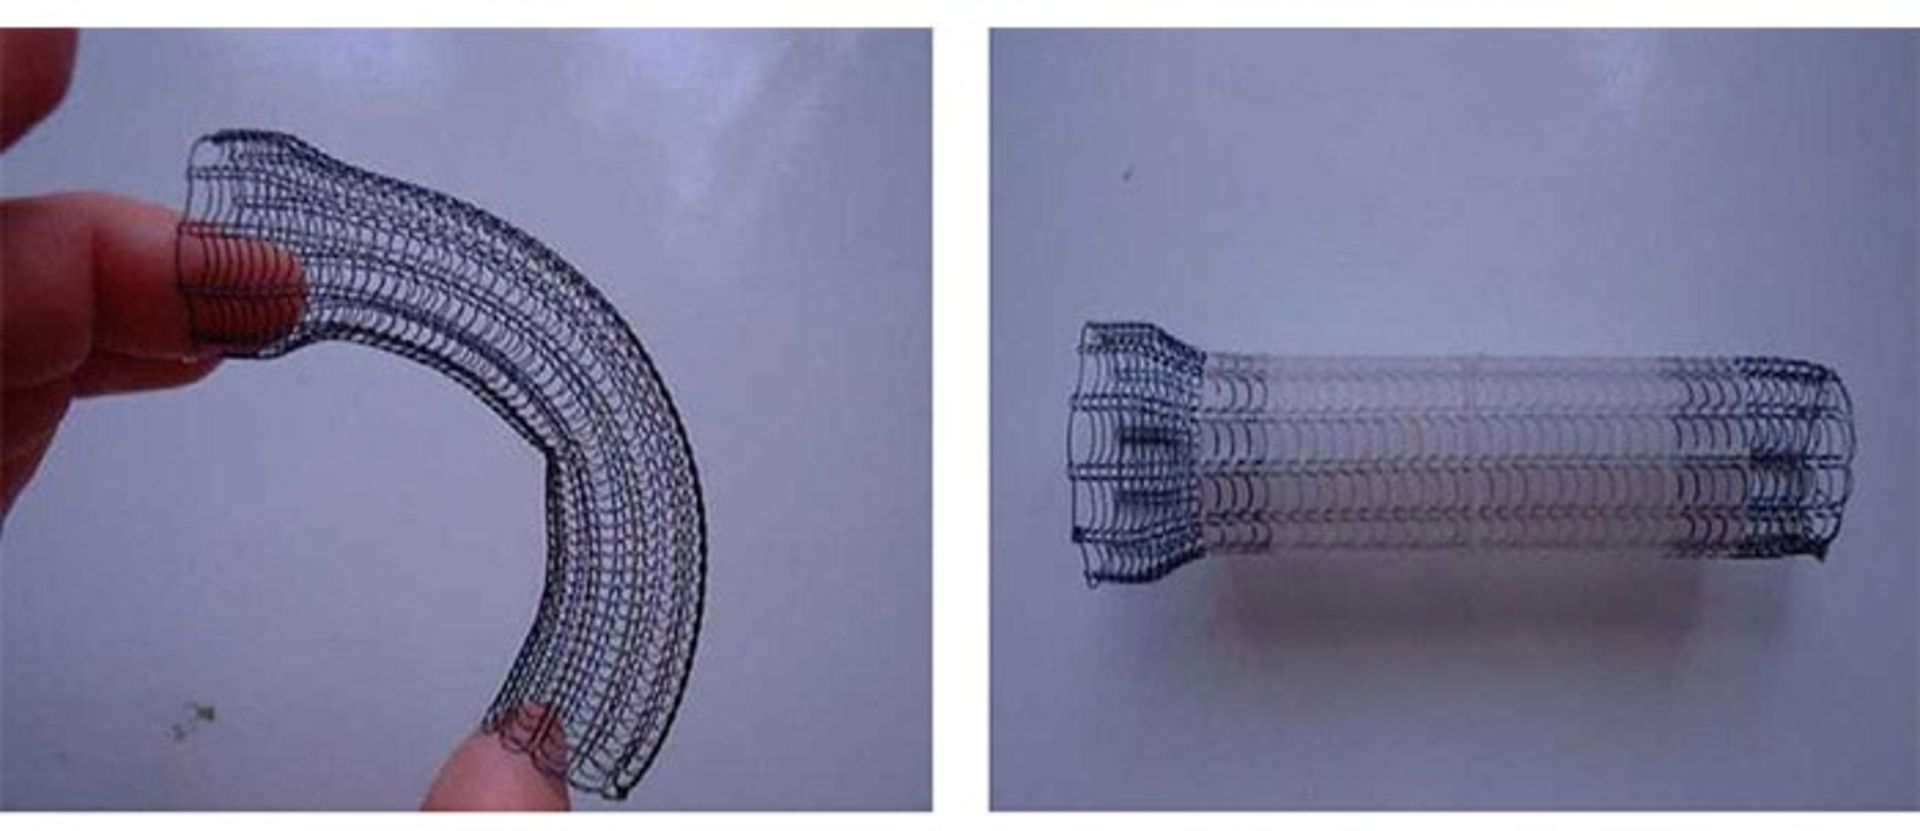

استنتگذاری

یک گزینهی دیگر برای پیشگیری از انسداد معده توسط تومور، استفاده از آندوسکوپ برای قرار دادن یک استنت (یک لولهی فلزی توخالی) در محل ورود معده به روده است. این کار موجب میشود این مسیر باز بماند و غذا از آن عبور کند. برای تومورهایی که در بخش فوقانی معده قرار دارند، این استنت در محل اتصال مری به معده قرار داده میشود. برای تومورهایی که در بخش تحتانی معده وجود دارند، استنت در محل اتصال معده و رودهی کوچک جای میگیرد.